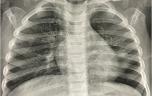

Inhalation d’un objet : tenter la manœuvre d’Heimlich en cas d’asphyxie

Inhalation d’un objet : QUE FAIRE ?